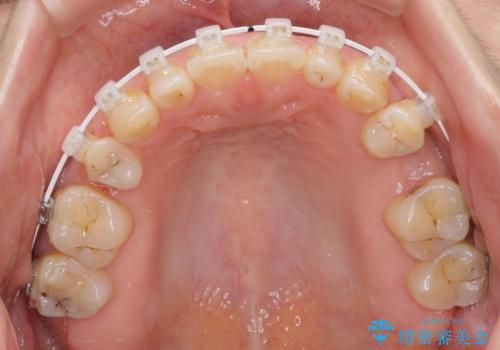

- 矯正装置

- 審美装置

歯列はワイヤー矯正にて改善することとしましたが、上下歯列にも隙間があったので、舌の突出癖を改善するトレーニングを徹底的に行うこととしました。

上顎のむし歯の酷い残存乳歯は抜歯をし、矯正治療の途中でインプラントを埋入、矯正治療後に補綴治療を行うこととしました。